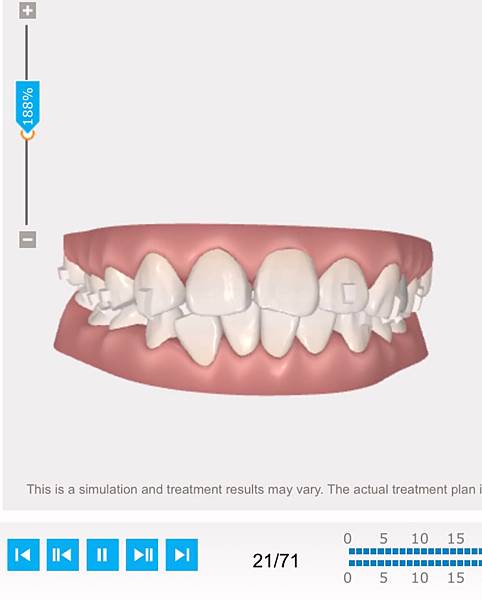

【中壢牙醫推薦】爵士牙醫 隱適美講師蔡孟桓醫師 牙套日記

【中壢牙醫推薦】打骨釘真的很可怕?! 爵士牙醫 蔡孟桓醫師 牙套日記2